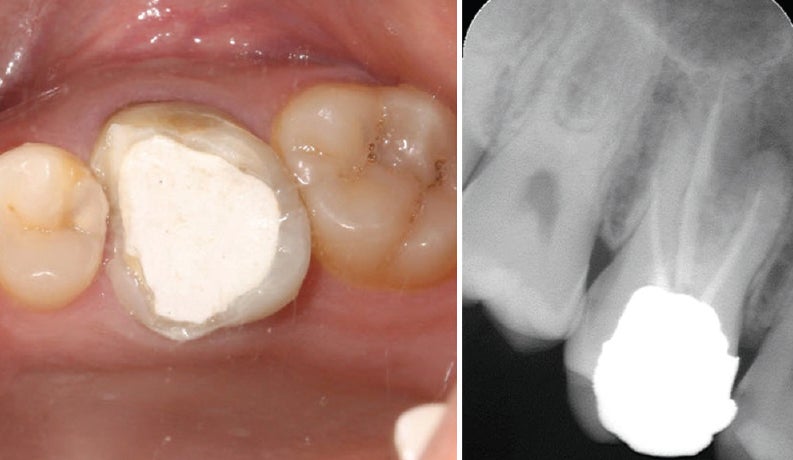

4. 치과 치료 절차 및 소요 비용

치과 치료 절차

- X‑ray 및 육안 진단 → 상태 확인

- 재접착 가능 시 임시/영구 접착 → 안 되면 새 크라운 제작

- 임시 크라운 장착 후 최종 크라운 장착 (1~2주 소요)